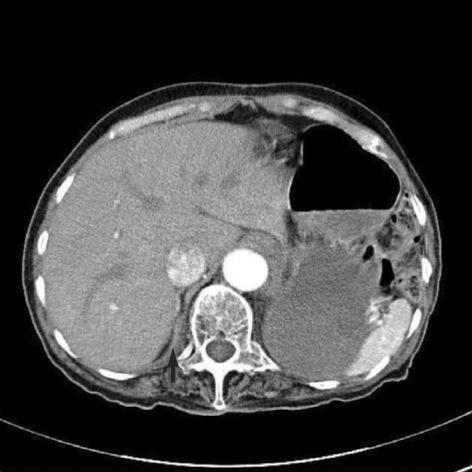

A 70-yr-old woman complained of left sided chest pain and non-bilious vomiting for four days after taking a gastric bloating agent for an upper gastrointestinal study. The chest radiography revealed gastric air-fluid levels and bowel loops in the left thoracic cavity. An emergency thoracotomy was performed. The abdominal organs (stomach, spleen, splenic flexure of the colon) were in the left thorax and the entire left hemidiaphragm was absent. There were no diaphragmatic remnants visible for reconstruction of the left diaphragm. We provided warm saline irrigation and performed a left lower lobe adhesiotomy. Thirteen days after surgery, the chest radiography showed improvement in the herniation but mild haziness remained at the left lower lung field. Here we present the oldest case of congenital diaphragmatic agenesis presenting with transient gastric volvulus and diaphragmatic hernia.

一名70岁女性在服用用于上消化道检查的胃胀气剂四天后,出现左侧胸痛和非胆汁性呕吐。胸部X线片显示左侧胸腔有胃内气液平面和肠袢。遂行急诊开胸手术。发现腹部脏器(胃、脾、结肠脾曲)位于左胸腔,整个左半膈肌缺如。未见膈肌残余组织用于重建左膈肌。我们进行了温盐水冲洗,并实施了左下叶粘连松解术。术后13天,胸部X线片显示疝出情况有所改善,但左下肺野仍有轻度模糊。在此,我们报告了年龄最大的先天性膈肌缺如病例,该病例表现为短暂性胃扭转和膈疝。